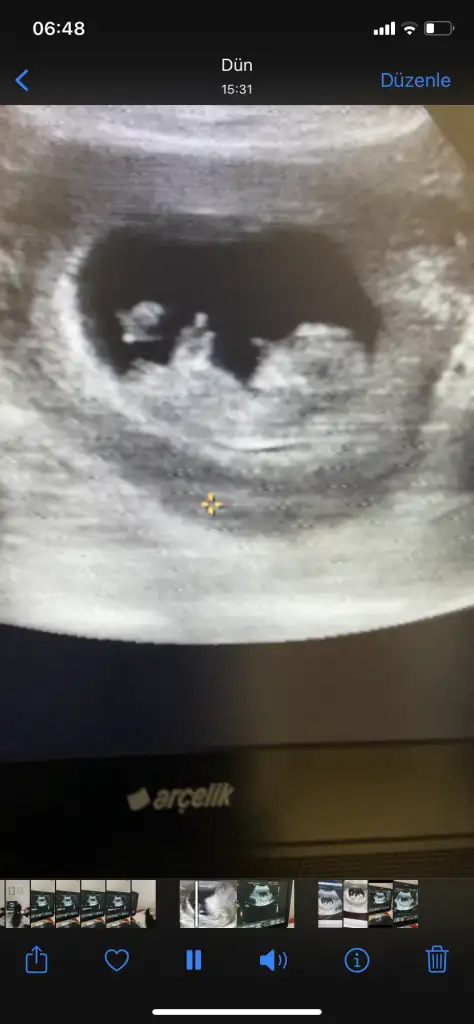

Erkek gibi canım bence6+1 haftalık görüntü cevap verebilecek olan var mıdır?karından ultrason

Önce kız sonra erkek demişsiniz sola tutuğundan erkek gibi düşündüm ben ama sizin son kararınız nedirErkek gibi canım bence

Pardon bana erkek demişsiniz yanlış anladımÖnce kız sonra erkek demişsiniz sola tutuğundan erkek gibi düşündüm ben ama sizin son kararınız nedir

Hayırlısı olsunPardon bana erkek demişsiniz yanlış anladım